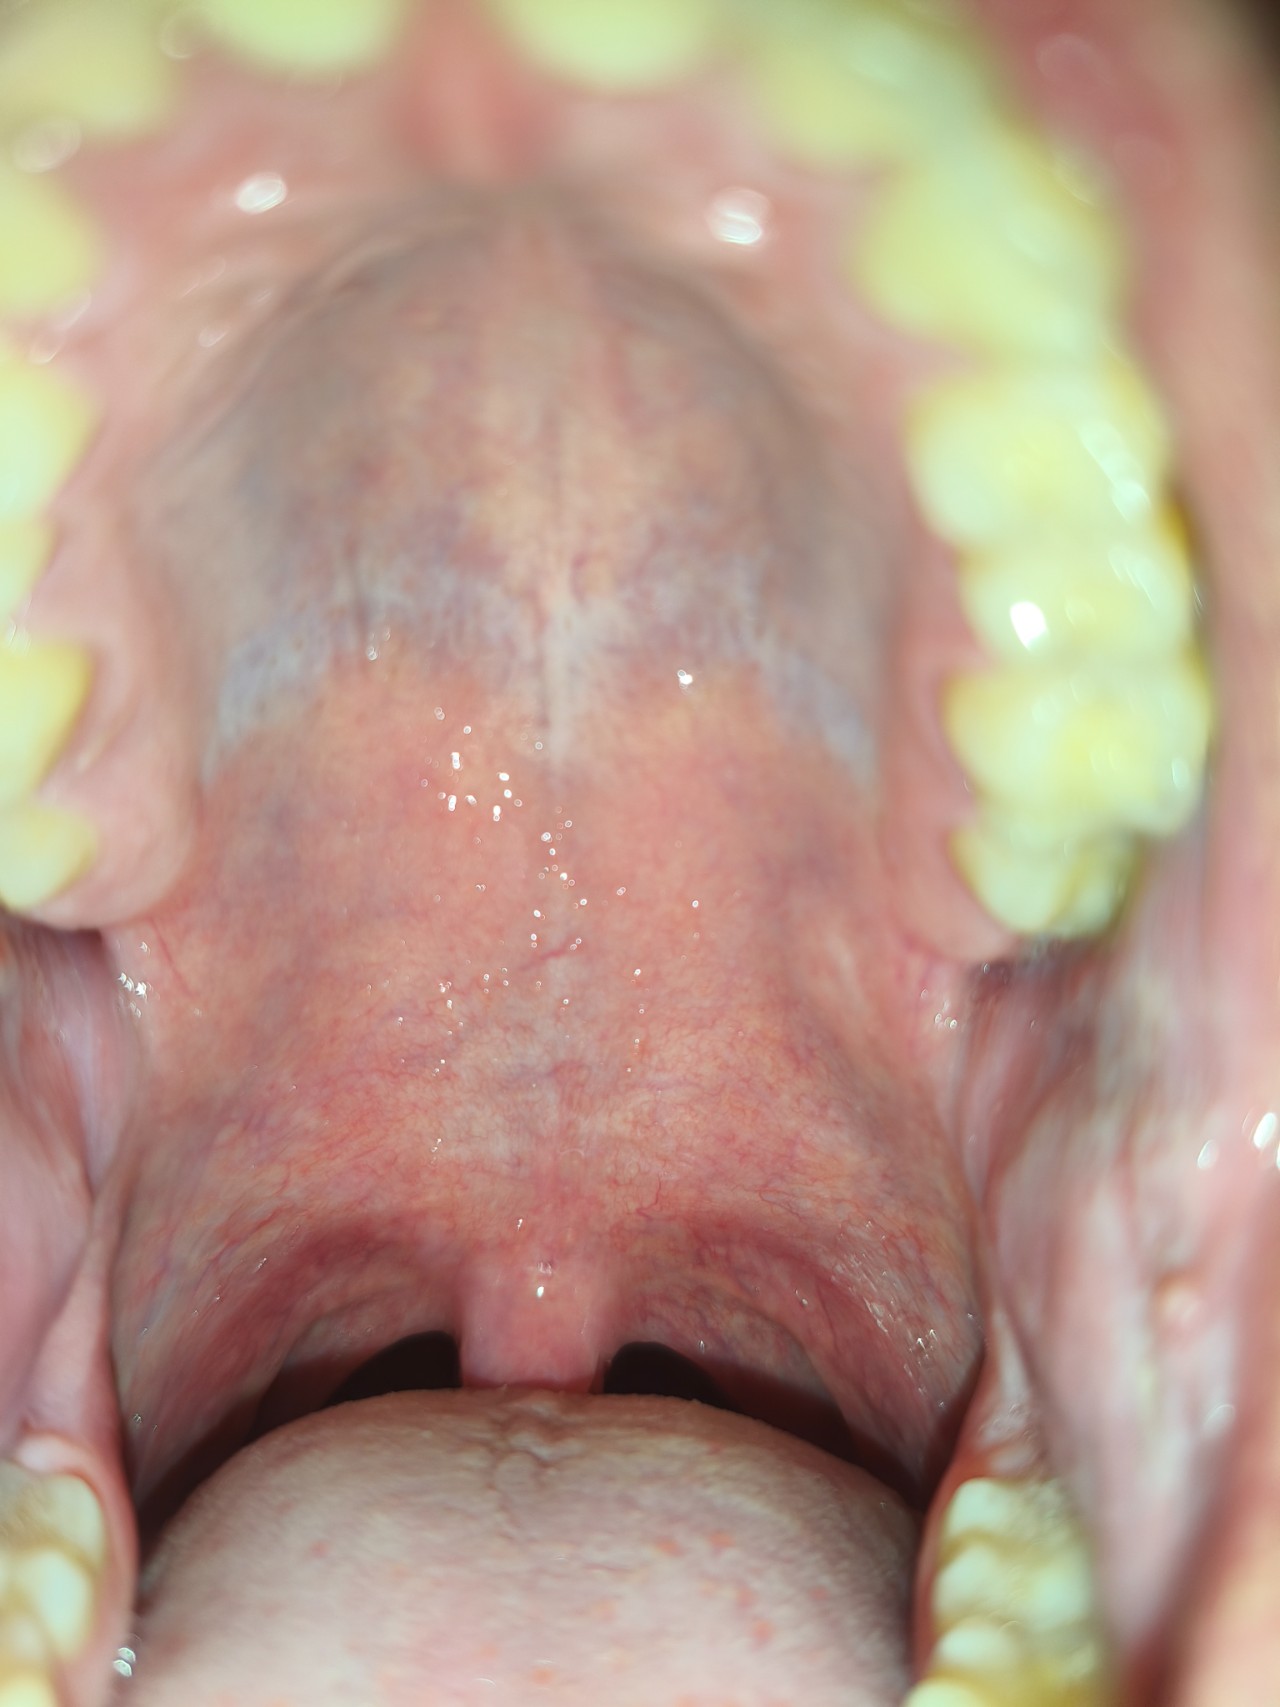

Здравствуйте, недавно заметил, что мое нёбо, ближе к зубам, серого цвета. Никакого дискомфорта не испытываю, это не налет. Подскажите, пожалуйста, чем это может быть вызвано.